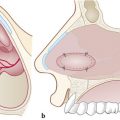

Blood supply of the nasal septum occurs through septal branches of the sphenopalatine artery. Here it anastomoses with branches of the palatine and labial arteries and septal branches of the anterior and posterior ethmoidal arteries; they are easily recognizable in the cranial portion of the septum area (Fig. 13‑1). An anatomical study on the arterial pattern of the nasal septum, traced by microdissection, demonstrated that AEAs were present in all cases, but the posterior ethmoidal arteries in some cases were absent. 1 These arteries, with the middle septal branch of the sphenopalatine artery and the superior labial branch of the facial artery, mainly contribute to the anastomotic triangle of the anterior septum. Only the posterosuperior area is vascularized by the posterior ethmoidal artery branches. 2 The ethmoidal artery originates from the terminal segment of the ophthalmic artery in the orbit cavity, a collateral branch of the internal carotid artery, and passes between the superior oblique and medial rectus muscle. The AEA then reaches the frontoethmoidal suture through the anterior ethmoidal foramen and enters into the anterior ethmoidal canal along with the anterior ethmoidal nerves. The artery crosses the ethmoid roof diagonally from posterolateral to anteromedial (Fig. 13‑2). AEA then divides at the lateral part of the cribriform plate of the ethmoid, giving off two or three branches to the mucosa of the cranial portion of the septum (Fig. 13‑3). Finally, they reach the olfactory cleft and supply terminal branches to the olfactory bulb and the meninges.

Based on the anatomical criteria of the nasal septum vascularization, characterized by the constant presence of the septal branches of the AEA, we harvested the monolateral mucosal flap with a large and flexible pedicle to bring a suitable blood supply to the flap. The extension to the inferior meatus creates a larger mucosal flap, allowing advancement of the flap without tension. 4